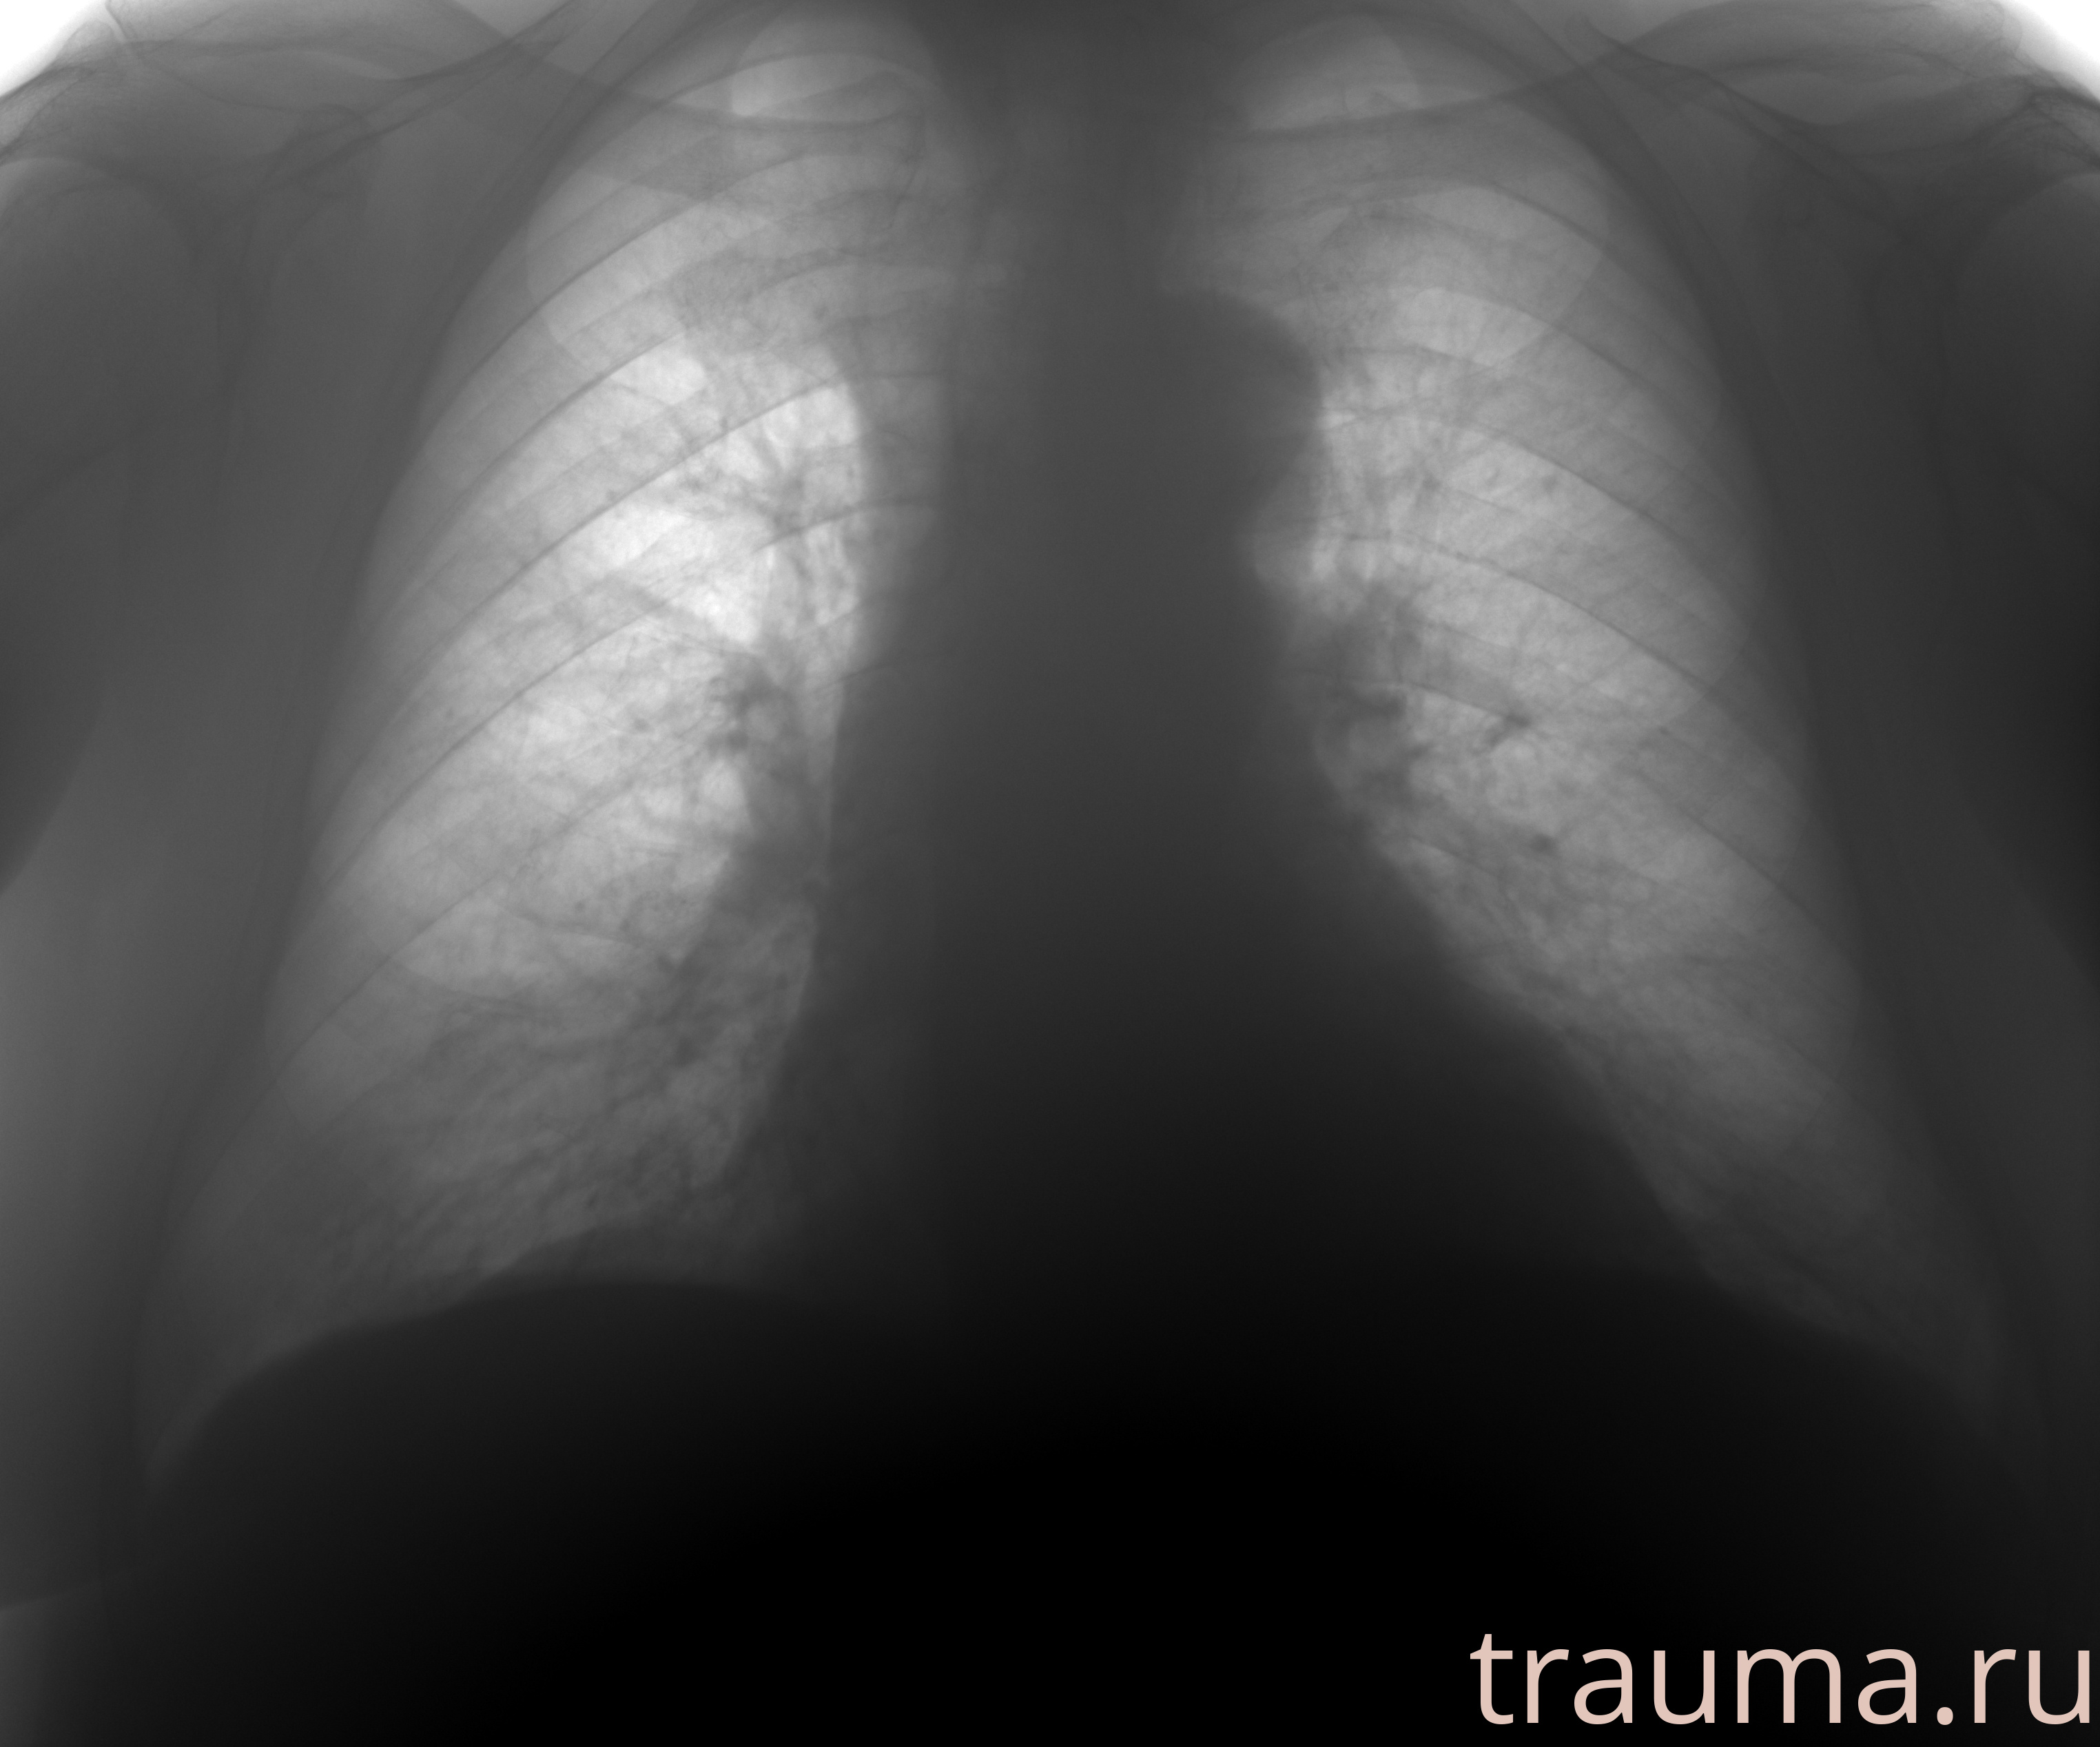

Рентгенограммы

Рентген на дому: по вашему адресу приезжает врач-рентгенолог, травматолог-ортопед с мобильным рентгеновским аппаратом, проводит диагностику травмы или заболевания, делает необходимые рентгенограммы, дает рекомендации по дальнейшему лечению. Получить качественные снимки в домашних условиях возможно благодаря уникальной методике, разработанной МосРентген Центром для института  Склифосовского

Яркость: 1   Контраст: 1   Инвертировать: 0 Увеличение: 1

Перетаскивайте мышь вверх/вниз для контраста, влево/право для яркости. Прокрутка колесом изменяет масштаб. Нажмите Сбросить для возврата к исходному изображению. При увеличении держите мышь в той области, которую хотите рассмотреть.